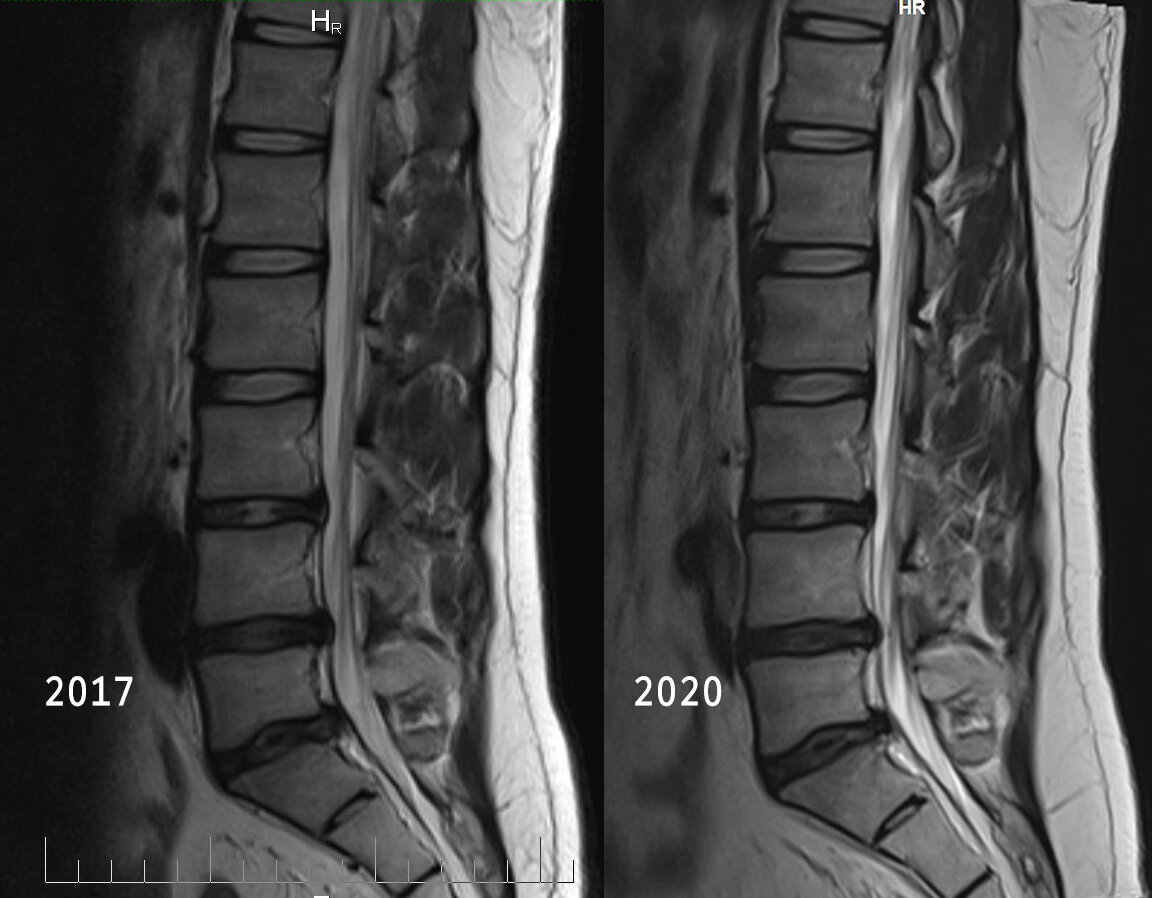

МРТ на 2ой день после операции. 2022г До и после. Более информативно будет через 3 месяца. Сейчас много отёков.